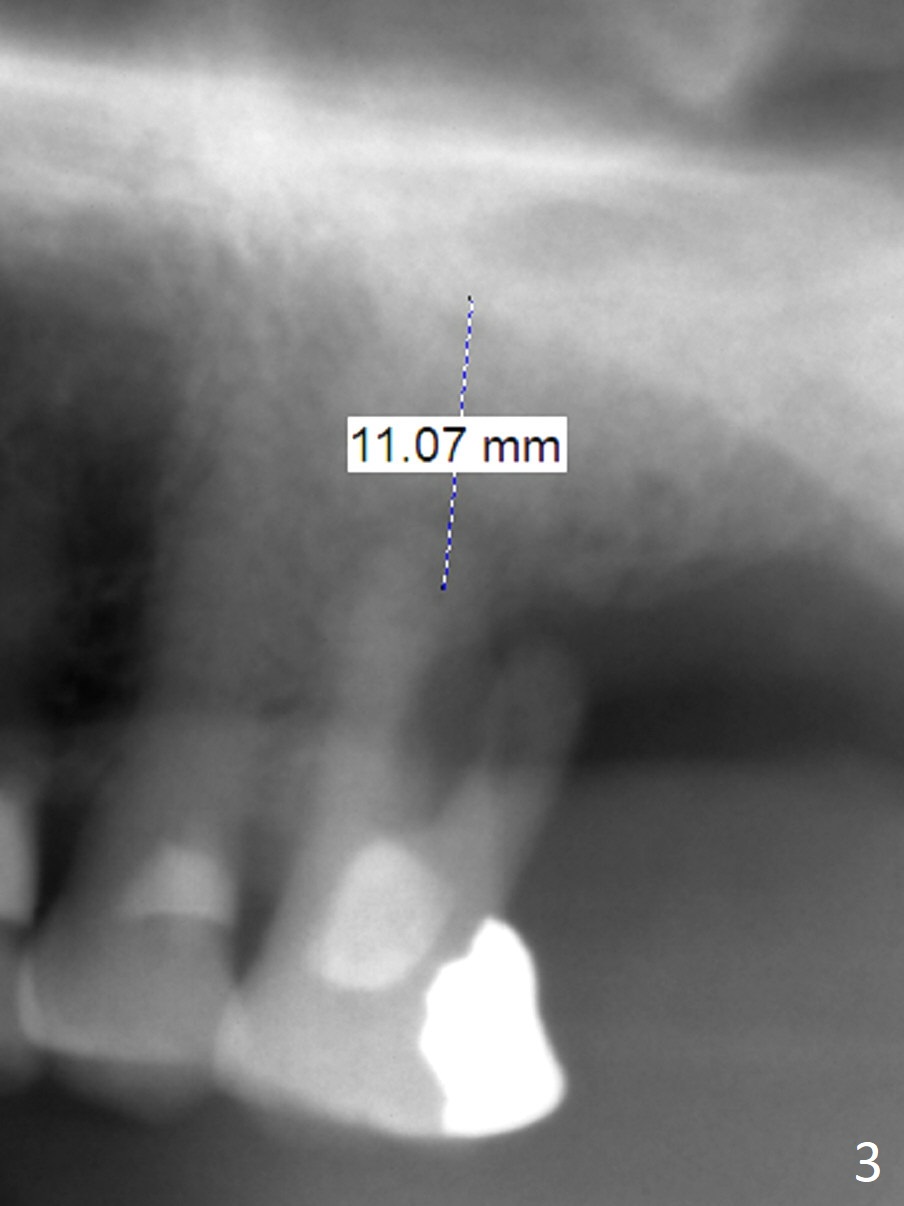

A 88-year-old man cannot masticate well on the left side because of the loose tooth at #14 with severe gingival recession buccal (Fig.1) and palatal (Fig.2 P). An implant will be placed in the septum; the peripheral defects of the sockets will be covered by PRF (x2) before bone graft. Initial depth of osteotomy will be 11 mm (Fig.3) with the implant length being 13 mm. Because of severe vertical bone loss, a mill abutment is expected (Fig.4). In fact CT shows the buccopalatal bone is wide. Use IS implant if it arrives. But cementation abutments are not available. A temporary abutment may be used. The patient is nervous about PRF.